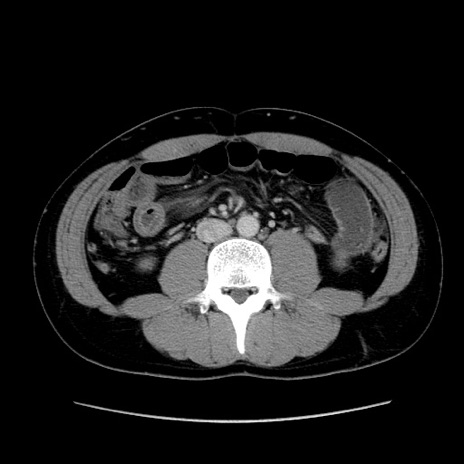

症例36(横断像)

【症例】20歳代 男性

【主訴】心窩部痛

【現病歴】今朝より上腹部痛あり。一旦軽快していたが再度出現したため救急要請。昨日夕に白身の魚を含む刺身を食べた。

【身体所見】BP 136/89mmHg、HR 74/min、BT 37.0℃、腹部:膨満、軟、心窩部に圧痛あり。反跳痛なし、筋性防御なし、腸雑音やや亢進あり。

【データ】WBC 17700、CRP 0.48